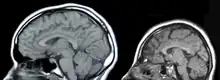

There are two parts of the nervous system: the central nervous system (CNS) and the peripheral nervous system (PNS). General body functions are supervised by the central nervous system (CNS), which includes the brain and spinal cord. The PNS delivers motor signals to control body activities and receives sensory data from the CNS. The PNS It is made up of nerve fibers arranged into nerves. The PNS's autonomic nervous system (ANS), whose sympathetic and parasympathetic branches preserve homeostasis and regulate involuntary physiological functions.[1]

There are four main causes of CNS injury: stroke, traumatic brain injury (TBI), brain tumors, or developmental complications. Strokes are classified as either hemorrhagic (when a vessel is damaged to the point of bleeding into the brain) or ischemic (when a clot blocks the blood flow through the vessel in the brain). When a hemorrhage occurs, blood seeps into the surrounding tissue, resulting in tissue death, while ischemic hemorrhages result in a lack of blood flow to certain tissues. Traumatic brain injury is caused by external forces impacting the cranium or the spinal cord. Problems with CNS development results in abnormal tissue growth during development, thus decreasing the function of the CNS.[16]